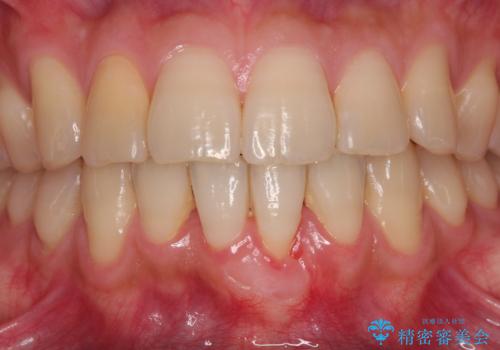

- 他院で矯正治療を終えた結果、下顎前歯の歯肉が退縮してしまい、歯根が見えていることが気になるとのことで来院された患者様です。

歯肉退縮に対して、上顎からの結合組織移植術(CTG)により、歯根の被覆を行うとともに、歯肉の厚みを増すことで将来の退縮リスクを抑制することとしました。